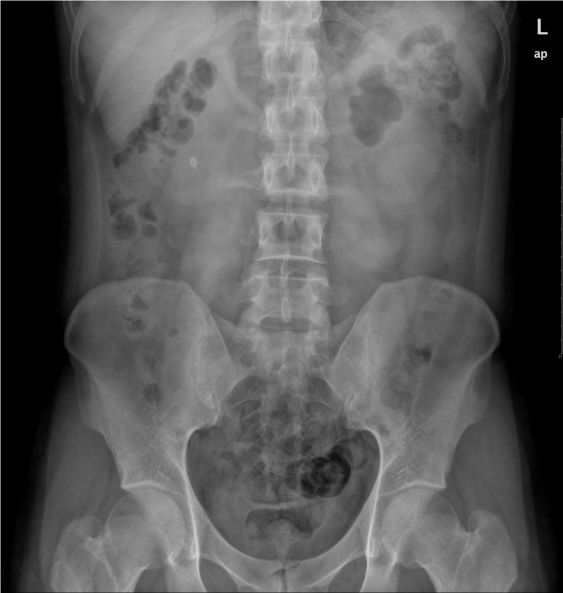

4)泌尿系结石:结石可见于肾、膀胱、输尿管和尿道的任何部位。临床表现因结石所在部位不同而有异。肾与输尿管结石的典型表现为肾绞痛与血尿,突发一侧腰部剧烈的绞痛,并向下腹及会阴部放射,伴有腹胀、恶心、呕吐、程度不同的血尿;膀胱结石主要表现是排尿困难和排尿疼痛。

X线腹平片,可以看到大部分的泌尿系结石,但对阴性结石无法显示。CT的诊断结果准确率最高,客观显示结石及积水情况。

右肾结石:腹部卧位平片可见右侧肾区结节状高密度影。